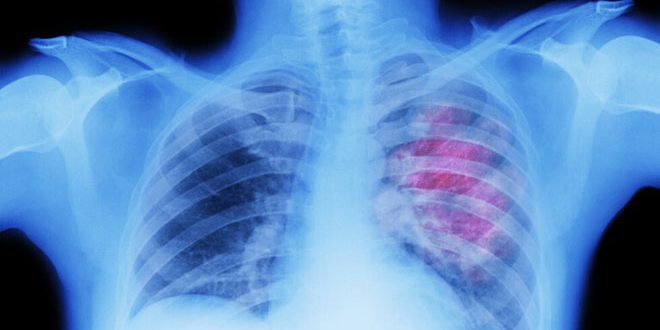

كشفت دراسة بريطانية جديدة أن واحداً من كل مئة مريض مصاب بفيروس كورونا يعاني ثقباً في الرئة ما زاد من تعقيد علاج المصابين.

ووجد الباحثون أن العدوى الشديدة لكوفيد19 يمكن أن تسبب تكيسات في الرئتين والتي قد تسبب بدورها تمزقات وثقوباً في الأنسجة الخارجية ولاحظوا معدلاً إجمالياً بنسبة 91ر0 بالمئة من المرضى المصابين بكورونا الحاد الذين يعانون ثقباً في الرئتين.